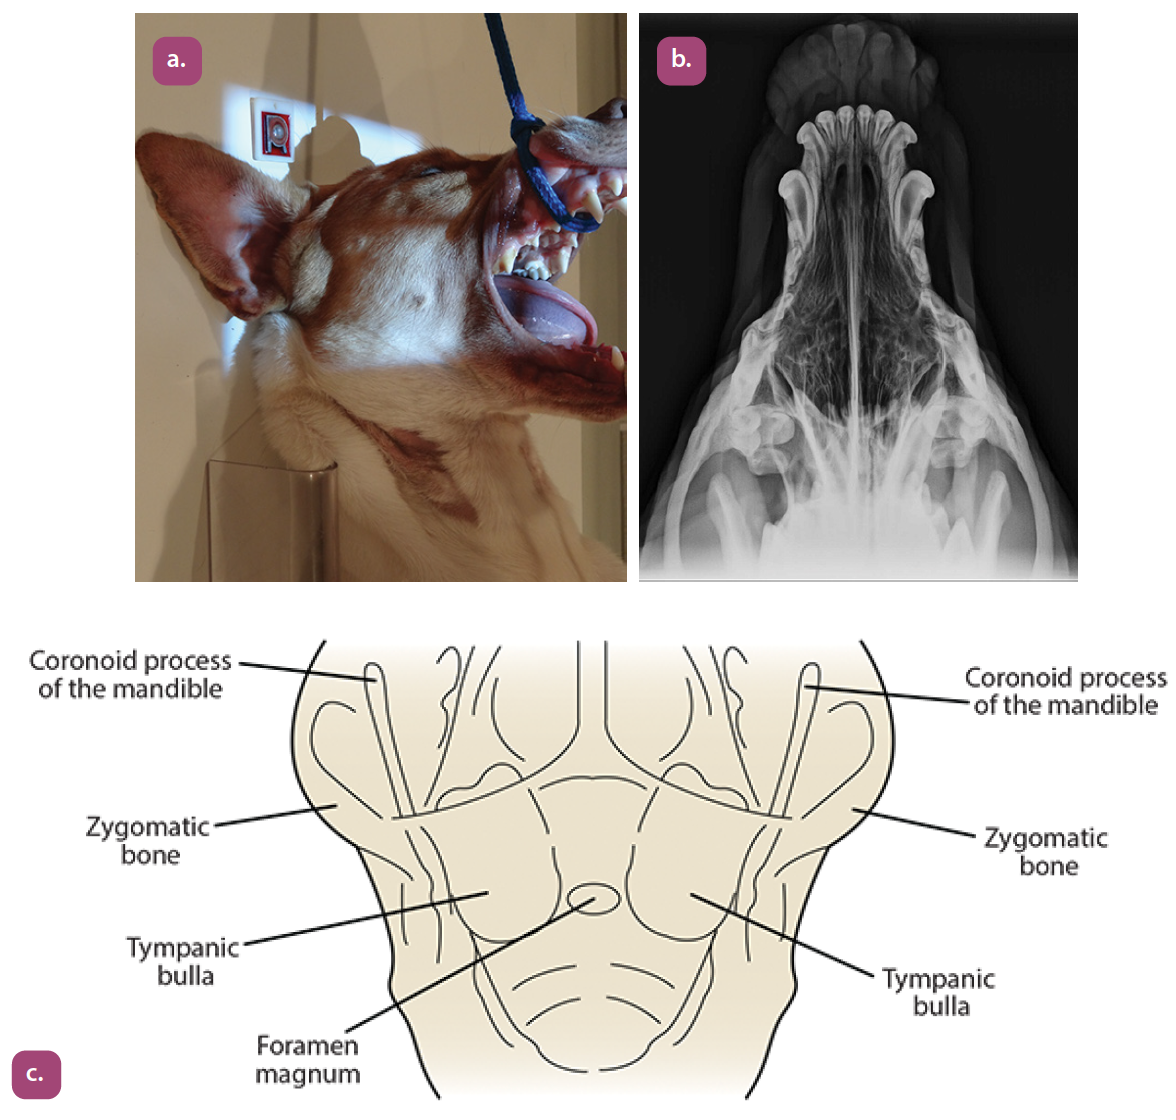

ventrodorsal rostrocaudal open mouth projection